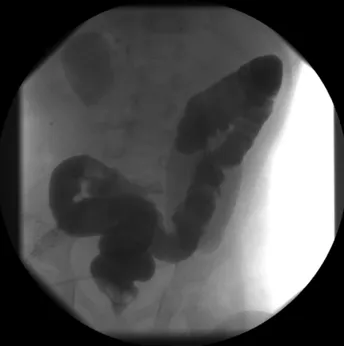

Standard illustrations of the colon[1] show the sigmoid colon looping just above the rectum, which it usually does.

No law, however, prevents the sigmoid colon from flopping over to the right side as shown here or in the X-ray above. [2] I suspected Ralph had this variation of his anatomy, and that most likely that he had an infected diverticulum in this part of his sigmoid colon.

Two days of antibiotics proved this assumption even more likely, because Ralph's fever disappeared and he felt much better. Once Ralph recovers entirely he'll get a barium enema to see if indeed he has diverticuli. Then we'll be better able to avoid further episodes and treat them more quickly should they occur.